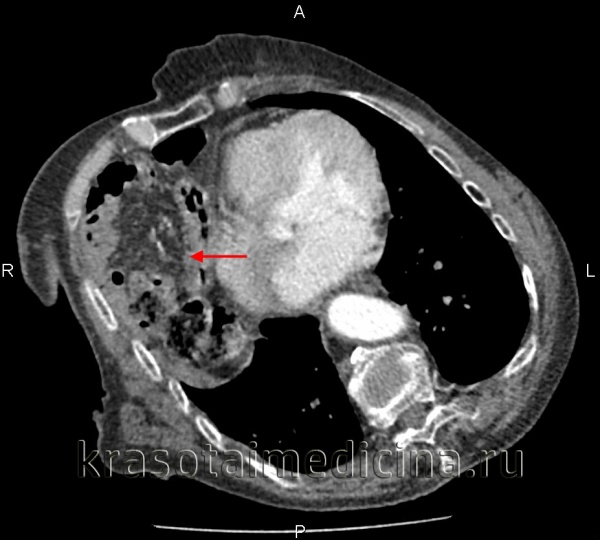

(Слева) На рентгенограмме грудной клетки у подростка, пострадавшего в ДТП, определяется пневмоторакс, плевральный дренаж и назогастральный зонд в виде извитой тени в проекции грудной клетки.

(Справа) На аксиальной КТ у этого же пациента определяются характерные признаки повреждения диафрагмы, в т.ч. симптом «выпадения» внутренних органов. Желудок находится в грудной клетке. Обратите внимание, что он прилежит к задним медиальным отделам грудной стенки. Желудок выглядит сдавленным в месте прохождения через дефект в диафрагме (симптом «воротника»). (Слева) На аксиальной КТ с контрастным усилением визуализируется желудок, находящийся в грудной клетке, выпавший через дефект в диафрагме. Желудок прилежит к задним медиальным отделам грудной стенки. Передняя стенка желудка, не ограниченная диафрагмой, напрямую соприкасается с легким.

(Справа) На корональной КТ у этого же пациента визуализируется желудок, выбухающий кверху сквозь дефектный участок в диафрагме.